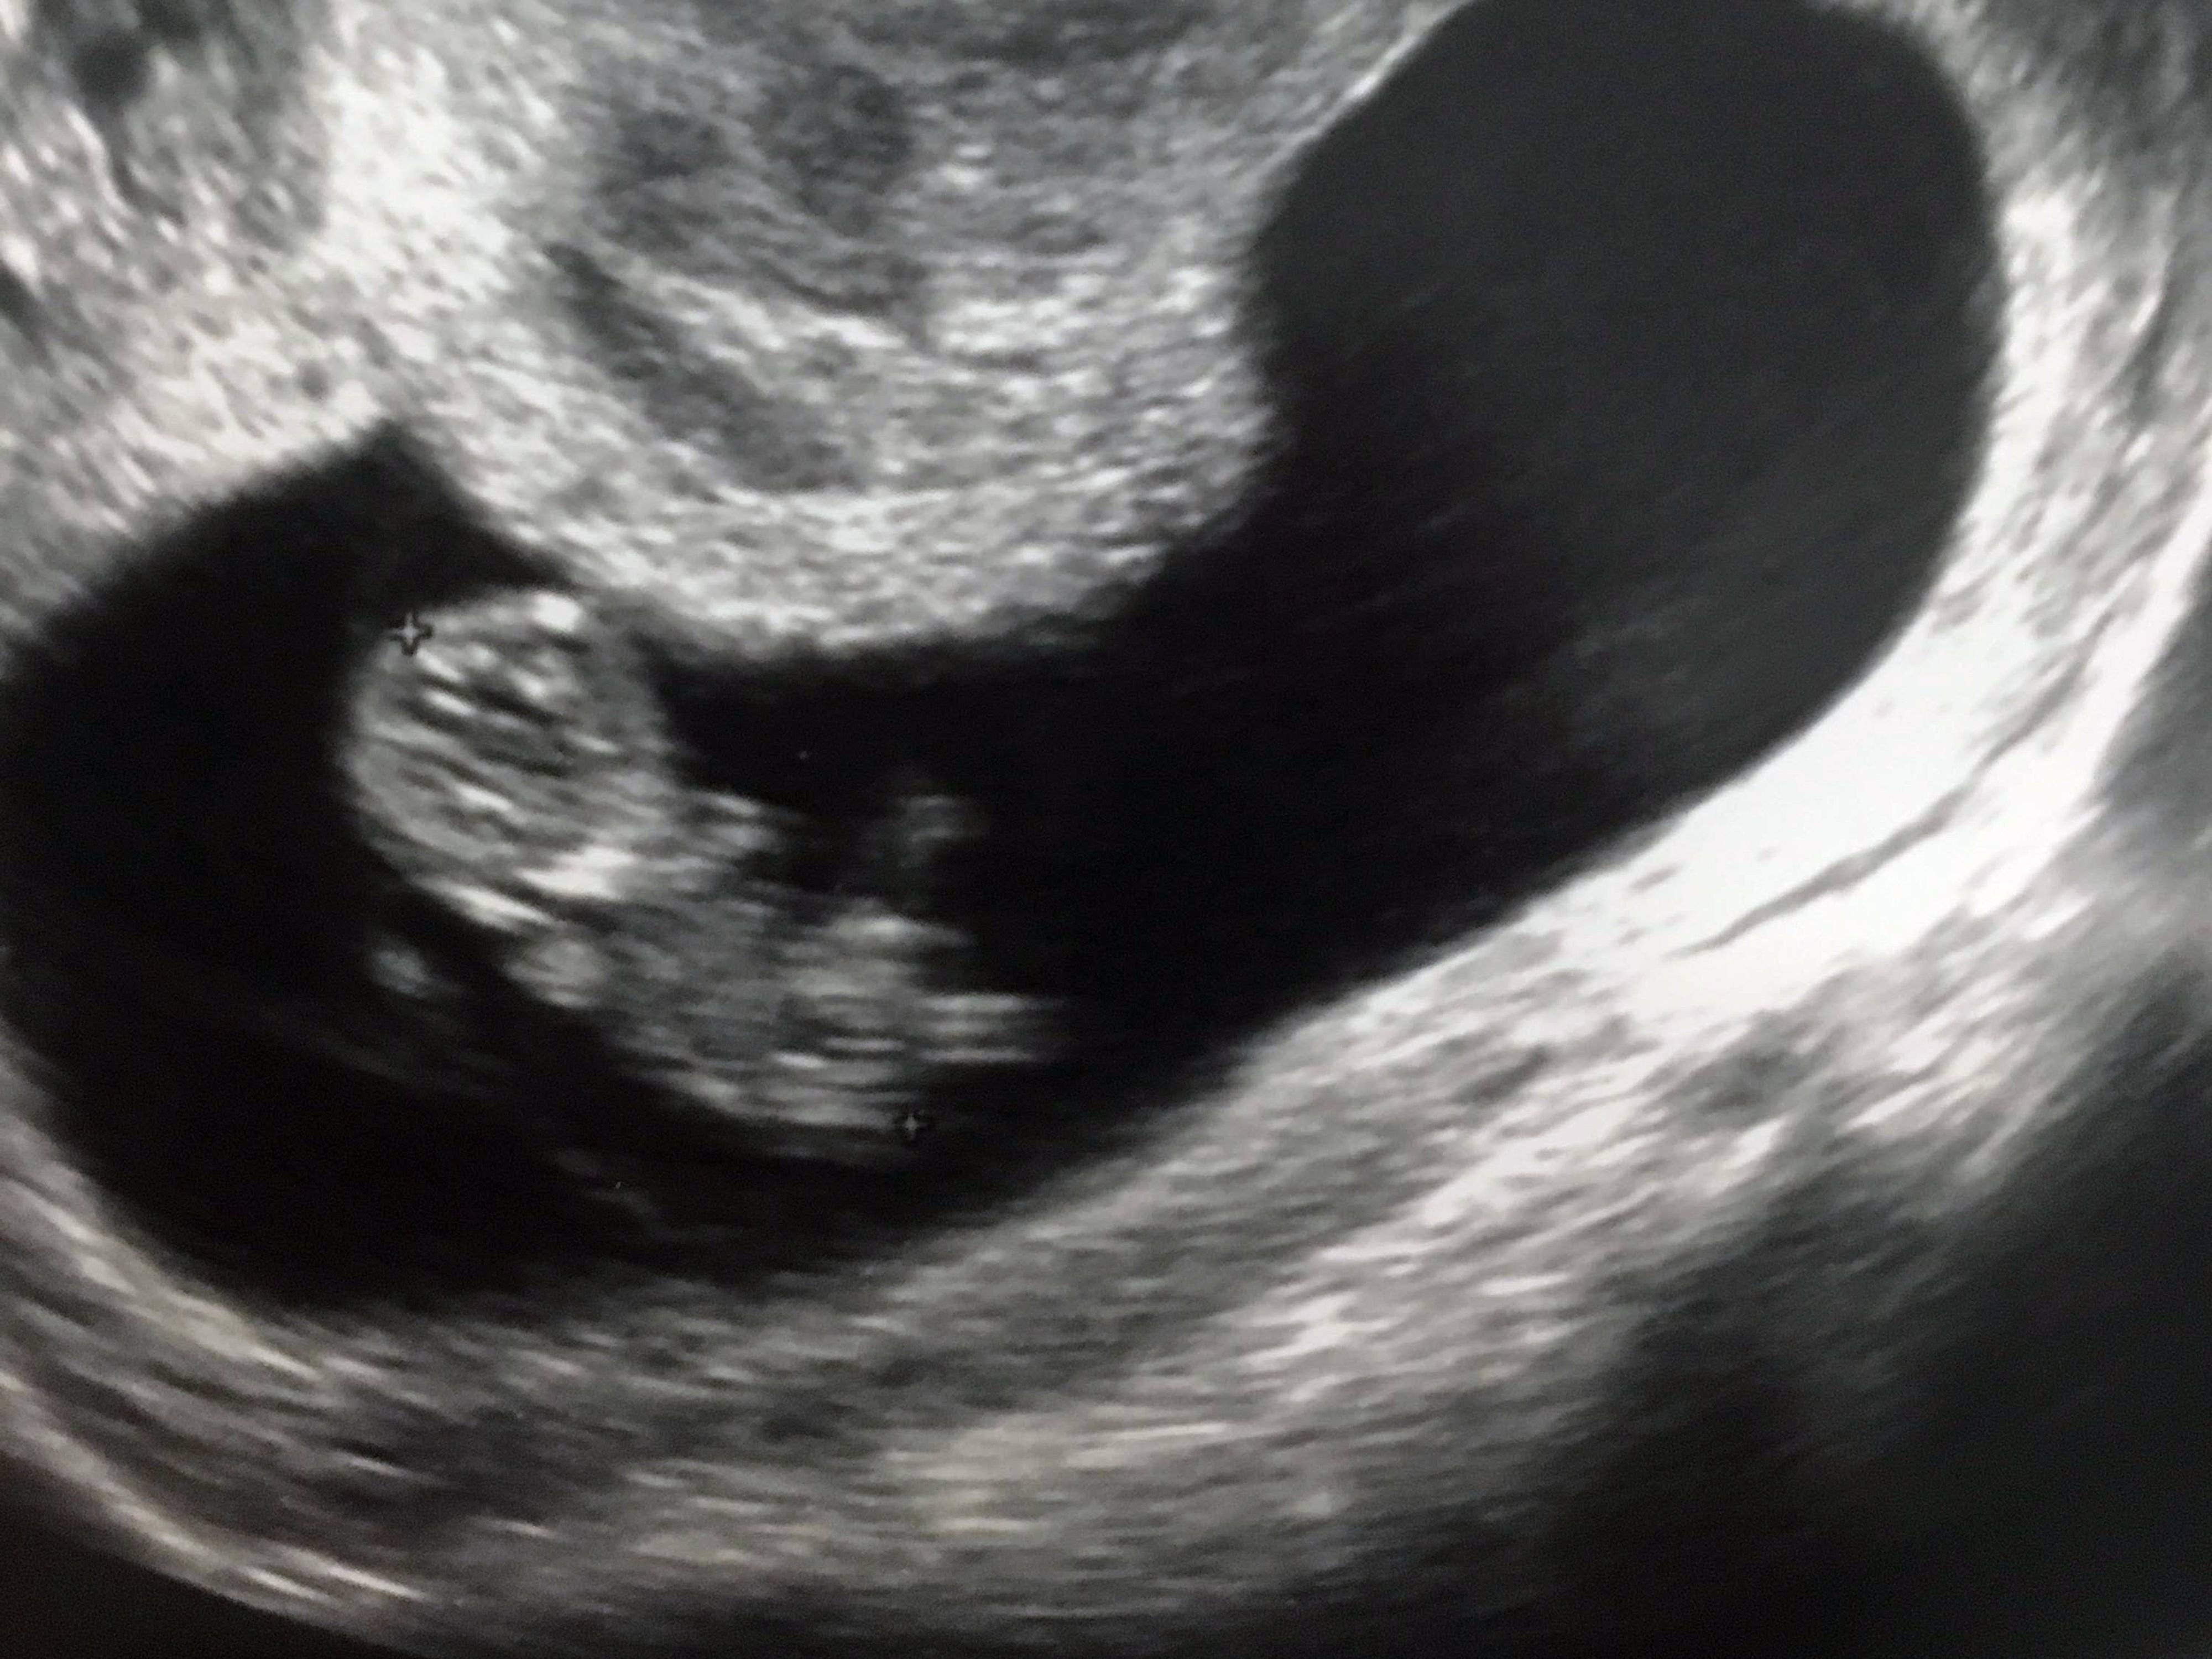

妊娠5週目 初めてのエコー写真!

妊娠検査薬で陽性確認をした翌日、初めての診察でもらったエコー写真です。

まだ胎嚢(矢印の先)しか見えませんが、感動して泣きそうになったことを覚えています。1週間後に心拍確認のため再度来院するよう指示され、無事に心拍を確認することができました。

心拍が確認できるまでは職場近くの婦人科で診てもらい、心拍確認後は自宅近くの病院で健診を受けました。